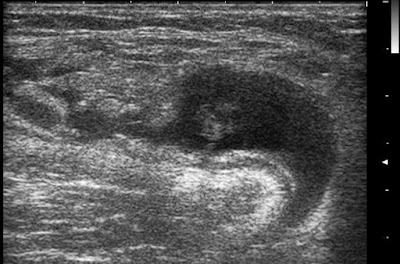

Baker cysta ruptura Szerző: admin | dec 11, 2010 | MSK | Nincsenek hozzászólások a Baker cysta falán megszakadás,a környezetében lapszerint elfolyó folyadék, a lumenében bevérzés 6×0 76573 2010.12.10